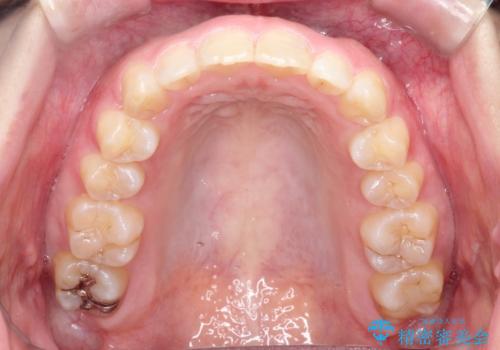

初診時の歯並びの状態としては、上の前歯が下に対して前に飛び出た上顎前突という状態で、前歯は大きく前に飛び出した状態により患者様も口の閉じづらさを感じているとのことでした。また上顎に軽度の叢生(ガタガタ)がありました。

抜歯は行わず上顎の奥のスペースを利用して歯をスライドする方法の他に歯列弓の拡大やディスキング(歯と歯の間の隙間を作る処置)を行い叢生を改善しました。

見た目、嚙み合わせ及び、治療期間や施術内容に大変ご満足いただきました。